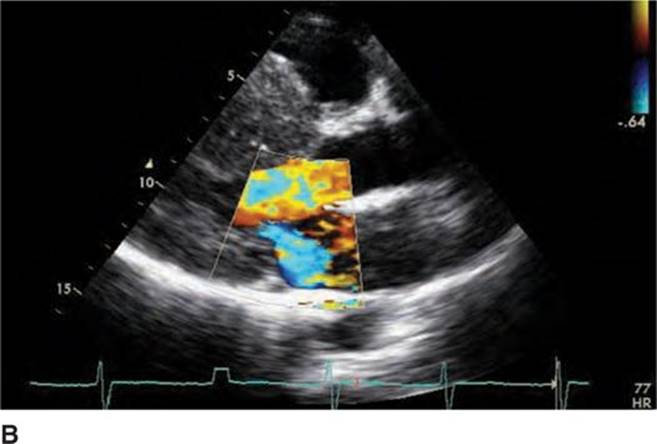

FIGURE 53-4B Parasternal long-axis view during systole with color Doppler demonstrating increased turbulent flow through the aortic valve with SAM and resulting mitral regurgitation.

Screening with transthoracic echocardiogram should be performed at the time of the initial evaluation and yearly thereafter in known HCM patients and is recommended at the time of initial screening of first-degree relatives to assess left ventricular systolic and diastolic function, wall thickness, and outflow tract gradients.1-3,5 The obstruction that occurs in HCM has been shown to be due to mitral valve systolic anterior motion (SAM) with mitral-septal contact (best illustrated in Figures 53-5 and 53-7B), muscular obstruction in the midcavitary region, or anomalous papillary muscle insertion into the anterior mitral leaflet.1,2,6 The peak LVOT or midcavitary gradient should be measured at rest, and if <50 mm Hg, the test should be repeated with provocative measures such as exercise, Valsalva maneuver, or potentially amyl nitrate, with the latter rarely required in the current era. Provocation with dobutamine infusion during echo is no longer recommended. Upon testing, one-third of patients will have a resting LVOT gradient >30 mm Hg (obstructive HCM), one-third will have resting gradients <30 mm Hg (nonobstructive HCM), and a final one-third will have normal resting gradients but provoked gradients >30 mm Hg (labile obstruction).1,2,6